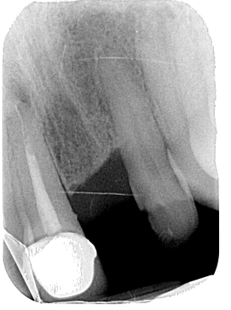

• Peri-apical lesion UR1 seen on radiograph

• RCT carried out 10 years ago

• Is the UR1 restorable?

CBCT scan OF UR1 Site, peri-apical cyst?

• Strict criteria is no periapical area present after rct. The meta-analyses had indicated that using strict criteria for judging treatment success, a minimum follow-up period of 3 years (Ng et al., 2007)